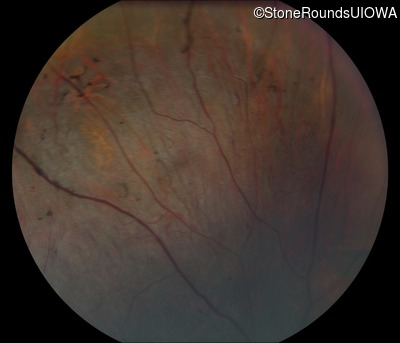

Fundus Photography - Right - 10/200

Exemplar